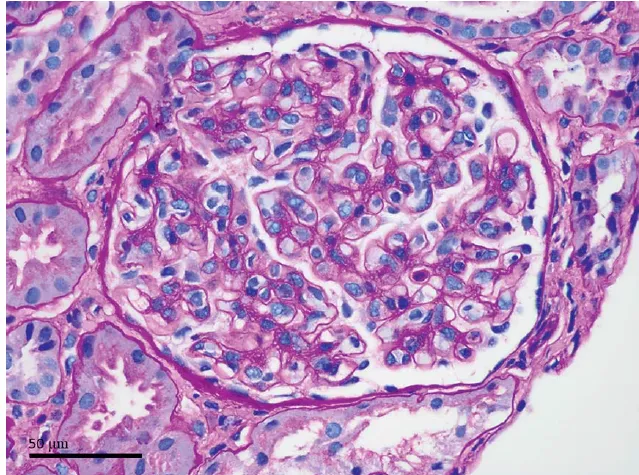

Uma causa incomum de hematúria glomerular intermitente!

Uma causa incomum de hematúria glomerular intermitente!

Hematúria pós infecção, caso clínicos para auxiliar no entendimento de causas glomerulares comuns e raras...